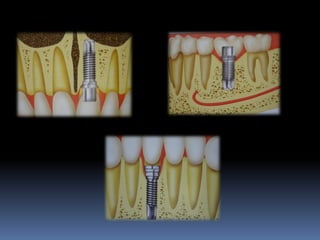

Ausência ou perda dental x implantes

Atrofias ósseas x implantes

Procedimentos reconstrutivos       Compensação protética

Atrofias óssea

Redução das dimensões ósseas ideais

•Estabilidade implantar

•Estética

•Função

Atrofias ósseas

•Procedimentos de enxertia óssea para

restabelecimento de dimensões perdidas

•Compensações dos tecidos perdidos nas

próteses